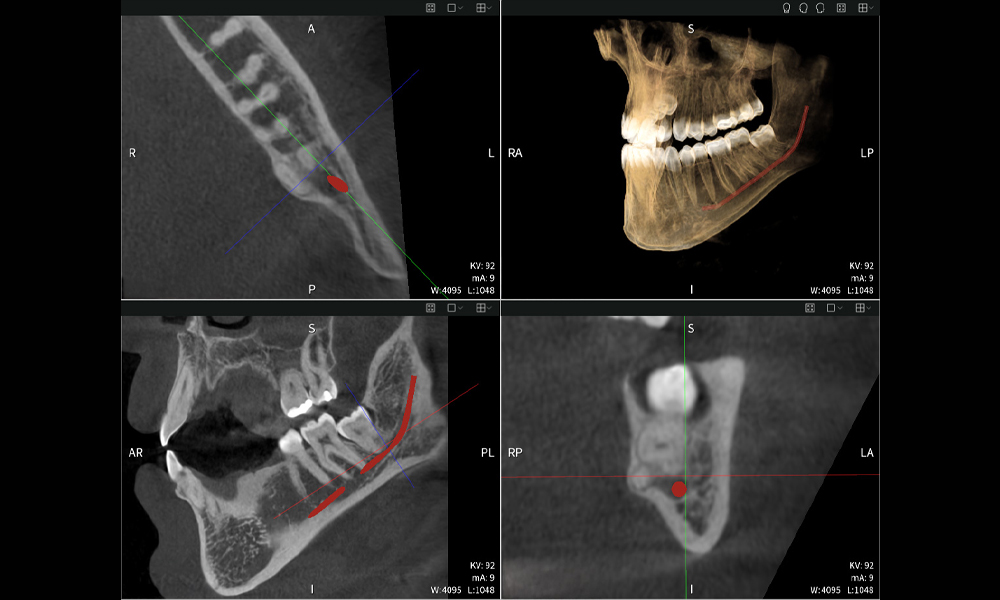

Nachstehend finden Sie einen Fall von Dr. med. dent. Oliver A. Centrella, in dem die CBCT-Aufnahmen mit Seethrough Max entscheidende Informationen zur komplexen Anatomie sowie zur kritischen Beziehung zwischen den Weisheitszähnen und dem Nervus alveolaris inferior lieferten. Bei diesem Fall besteht eine Indikation zur chirurgischen Entfernung der Weisheitszähne.

- Oben links: Axiale Schnittansicht des linken Unterkiefers (Region 38) mit Darstellung des Nervus alveolaris inferior (rot) in unmittelbarer Nähe zu den Wurzeln des Zahns 38.

- Oben rechts: 3D-Rekonstruktion des gesamten Unterkiefers zur Orientierung. Der rot markierte Nervus alveolaris inferior verdeutlicht seine Lage im Kieferknochen.

- Unten links: Sagittale Ansicht des Unterkiefers (Region 38), die die enge räumliche Beziehung zwischen den Wurzeln und dem Nervenkanal verdeutlicht.

- Unten rechts: Koronale Ansicht des Unterkiefers (Region 38) entscheidend für die Beurteilung der räumlichen Lage der Wurzeln zum Nerven.